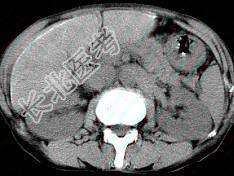

- 单项选择题男,40岁有血吸虫感染史, 腹胀不适,食欲减退, CT扫描所见如图,最可能的诊断是 ( )

A、肝炎后肝硬化

B、血吸虫后肝硬化

C、酒精性肝硬化

D、胆汁性肝硬化

E、脂肪肝